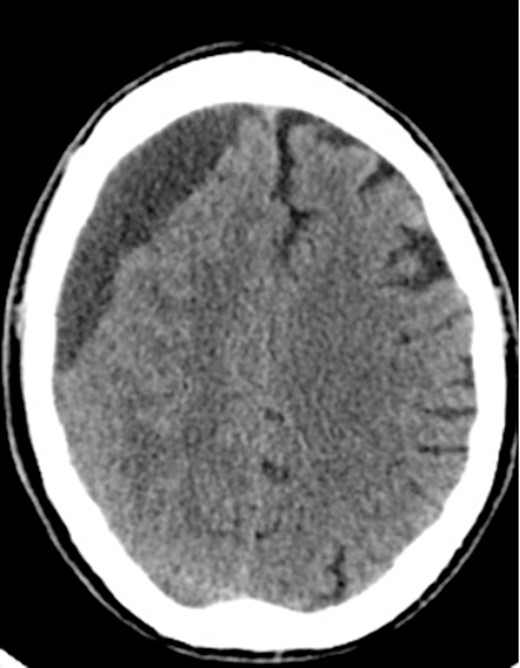

A 60-year-old male with cSDH presented to a Level I trauma center with lethargy, headaches, and left-sided hemiparesis. CT demonstrated thickened membranes and midline shift (Fig. 1).

An AR system was used to register the patient’s 3D anatomy onto the patients’ head (Fig. 2). Burr hole locations were annotated onto the registered 3D model to assist with craniotomy planning. Visualization of the 3D model confirmed plans for safe burr hole placement away from the dural venous and bony sinuses for a right frontoparietotemporal craniotomy. The AR headset was used once again to visualize the hematoma, vascular structures, and to confirm proper burr hole locations. The evacuation of the subdural hematoma was performed. Eight burr holes were placed, and a 14 × 11 cm bone flap was elevated to access the dura. The dura was then opened in a curvilinear fashion and hinged over the superior sagittal sinus. The cSDH was identified by its thick parietal and visceral membranes and underlying liquefaction, and these anatomic layers correlated directly with the AR overlay. The membranes of the hematoma were resected with the cortex demonstrating no gross abnormalities. The wound was irrigated, and the dura was closed primarily. The bone flap was then secured with two central tack-up structures followed by titanium reconstruction with multiple burr hole covers. There were no intraoperative complications, and the patient tolerated the procedure well with improved strength and decreased headache postoperatively. Post-operative CT showed interval decrease in the mixed-density subdural collection and reduced midline shift (Fig. 3).